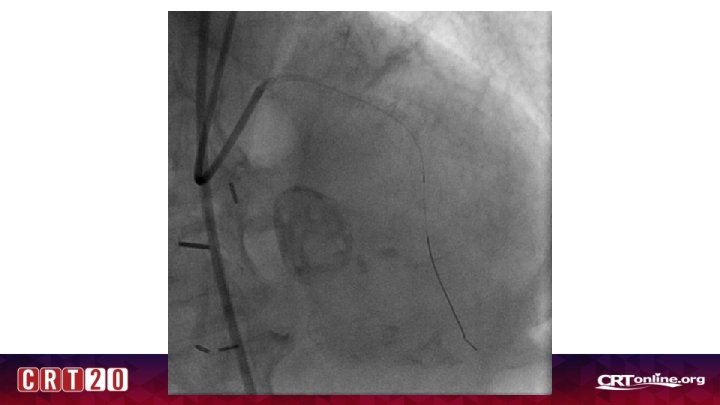

Where is the culprit?

Unclear Culprit